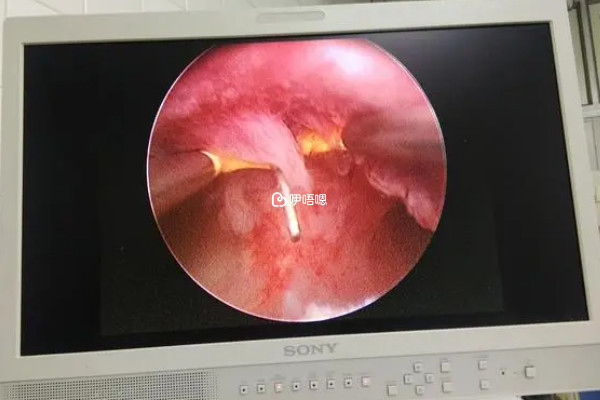

宮腔鏡手術後能否走路回家,取決於患者對手術的耐受能力,一般是不建議手術就直接走路的,宮腔鏡手術過程中的膨宮操作和牽拉宮頸操作,可能會引發腹部疼痛、噁心嘔吐、陰道流血等症狀,如果患者耐受能力較差,以上症狀十分明顯,需要臥床休息30分鐘到2小時。

宮腔鏡手術屬於微創手術,一般來說,對子宮造成的創傷較小,如果患者耐受能力較強,覺得手術後無任何不適,或者不適的症狀能夠忍受,患者可以正常行走,做完宮腔鏡手術,有很多注意事項,如果不注意可能會引起併發症,宮腔鏡手術後注意事項為: